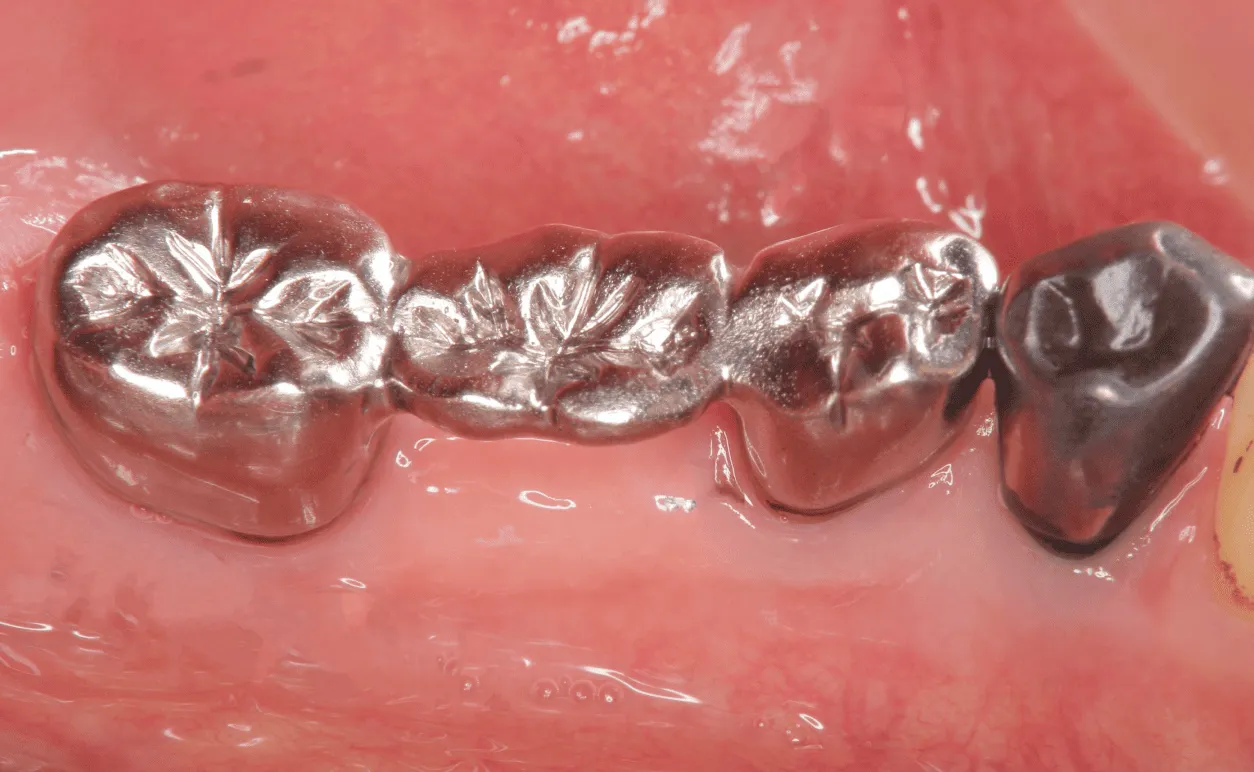

• 保険のむし歯治療

銀歯やプラスチック

保険のむし歯治療は、レジンや金属など標準的な材料で低コストに対応可能です。ただし、美しさや耐久性に限りがあり、金属の場合はアレルギーのリスクがあります。